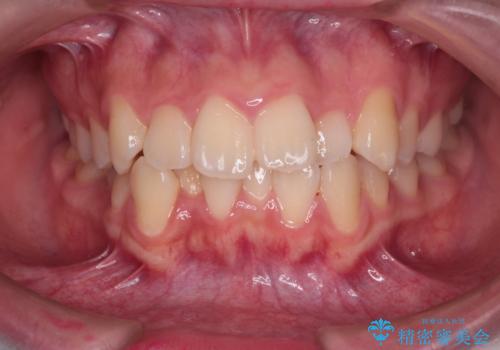

【インビザライン】前歯の凸凹を非抜歯で治療

- 前歯の凸凹を主訴の来院されました。

奥歯を後ろの方に移動させるために矯正用のアンカースクリューを使いながら治療をおこないました。

患者さんの都合により、マウスピースの装着時間が不足したため、途中からワイヤーにて治療を行いました。